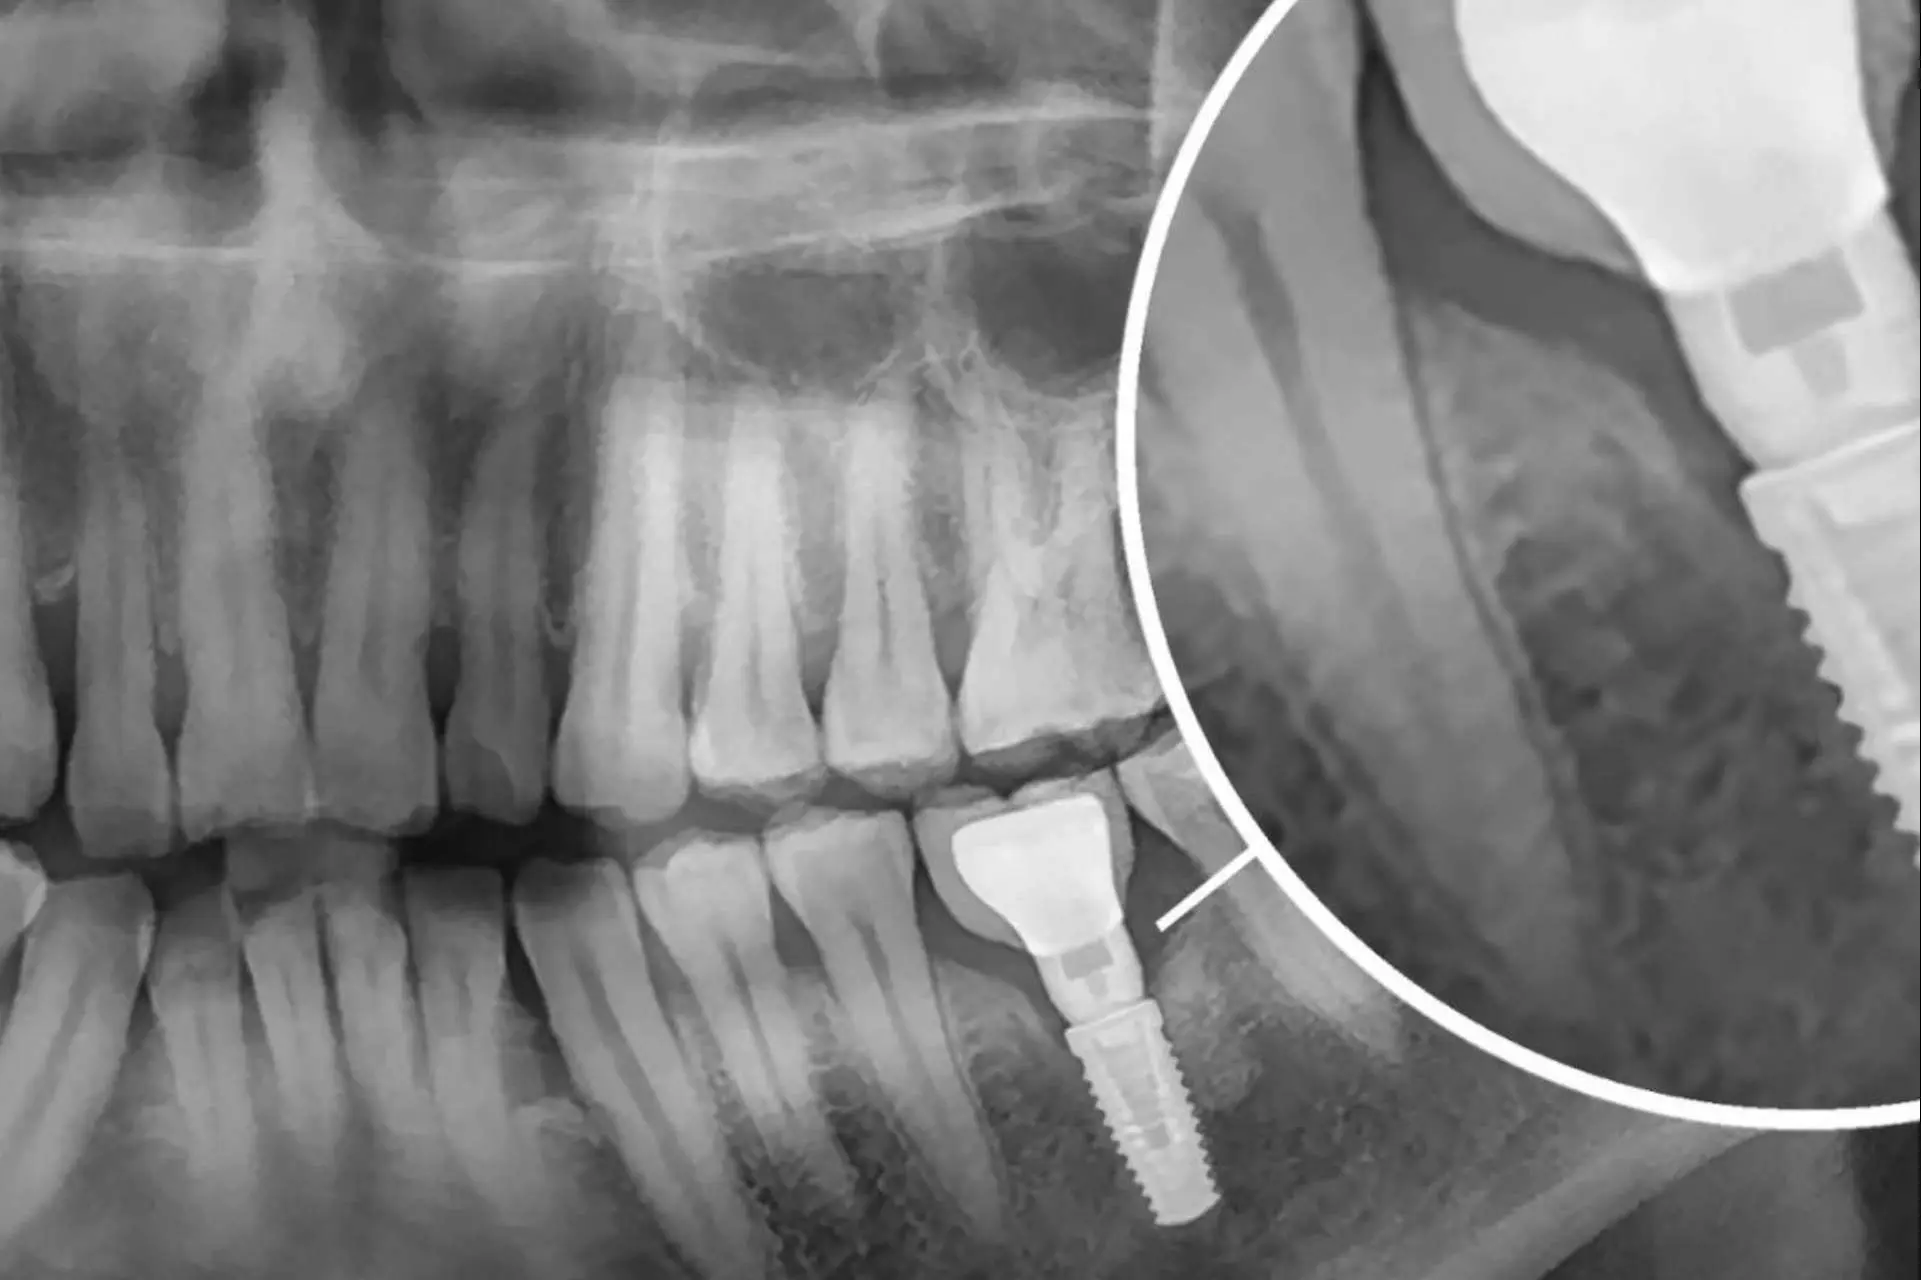

La propuesta de la Clínica Dental Dr. Román Hernández resalta por dar inicio con una revisión dental completa de la boca que detalla el estado de cada paciente para proceder al procedimiento más idóneo. Seguidamente, se lleva a cabo un estudio radiológico que muestra los tejidos óseos en cuanto a cantidad y calidad del hueso. Cuando dichos estudios finalizan, se procede a determinar el tipo de implante ideal, sea implante unitario, puentes dentales, prótesis dentales o injerto de hueso.